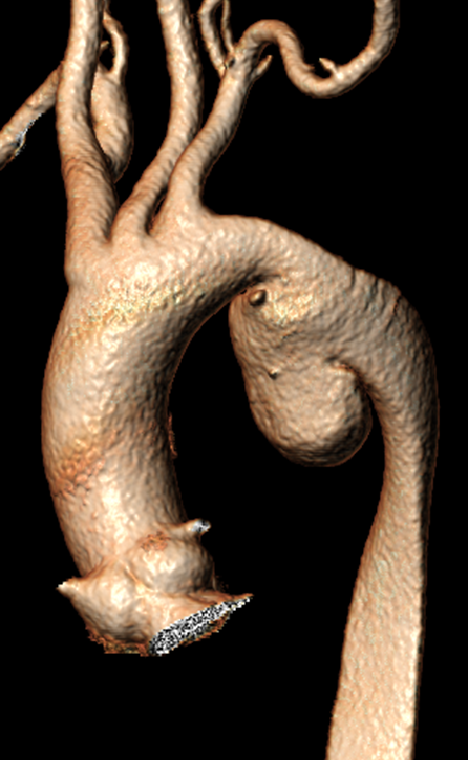

ZIPPERTM支架系统(Zhang Invented Percutaneous Permanent Endovascular Repair, ZIPPERTM Endograft System)是张玮教授团体自主研发的完全经皮经股动脉治疗主动脉弓部病变的新型支架。

① 预弯主体支架,可防止主体支架翻转

② 可调弯输送系统,适用于不同主动脉弓型、适用于急诊手术

③ 预置头臂动脉导丝

与近端主体支架成30°角分离

避免导丝缠绕

④ 近端主体支架可控

⑤ 前端后释放系统,可避免心脏停跳及脑缺血

⑥ 灵活可调节的头臂动脉分支

⑦ 灵活的左颈总动脉分支

⑧ 漏斗形的左颈总动脉和左锁骨下动脉支架开口便于分支选择

⑨ 现货成品供应的支架系统适合大多数的主动脉弓解剖结构

目前ZIPPERTM支架系统已应用于临床试验,体现出完全微创、操作简单、疗效确切、安全等优点。[3,4]

[3] Dong, Honglin et al. “First-in-man ZIPPER™ endograft system for the treatment of symptomatic aortic arch intramural haematoma.” European heart journal. Case reports vol. 7,11 ytad574. 17 Nov. 2023, doi:10.1093/ehjcr/ytad574

[4] Fu, Weiguo et al. “Total Percutaneous Transfemoral Endovascular Treatment of Non-A Non-B Aortic Dissection.” JACC. Case reports vol. 30,1 102756. 4 Dec. 2024, doi:10.1016/j.jaccas.2024.102756